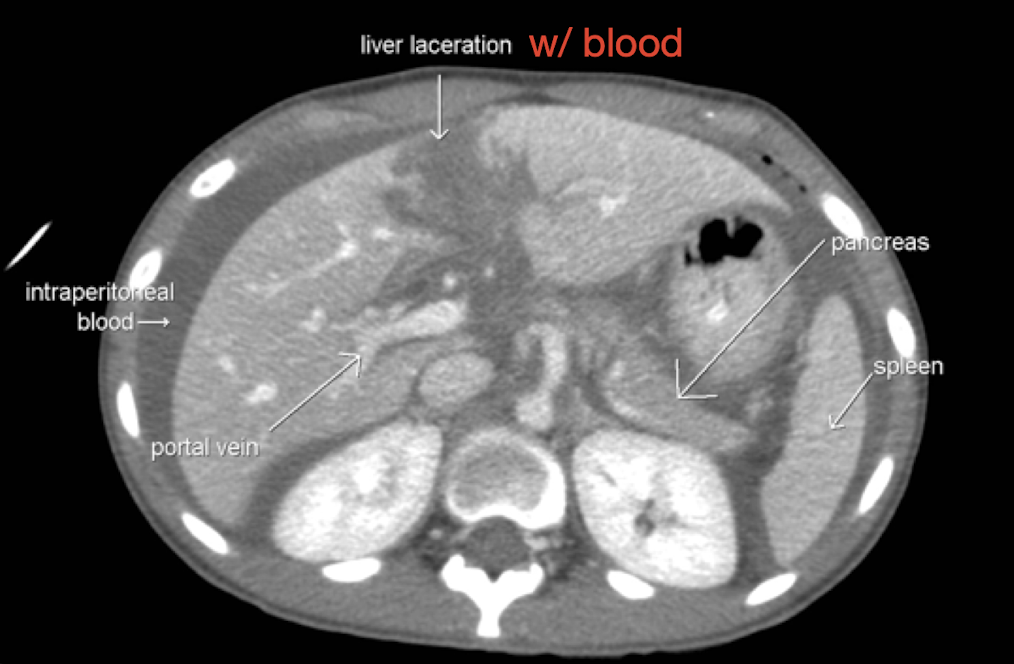

Trauma: Liver

CTA Abdomen/Pelvis IV contrast

Trauma: Spleen

CTA Abdomen/Pelvis IV contrast